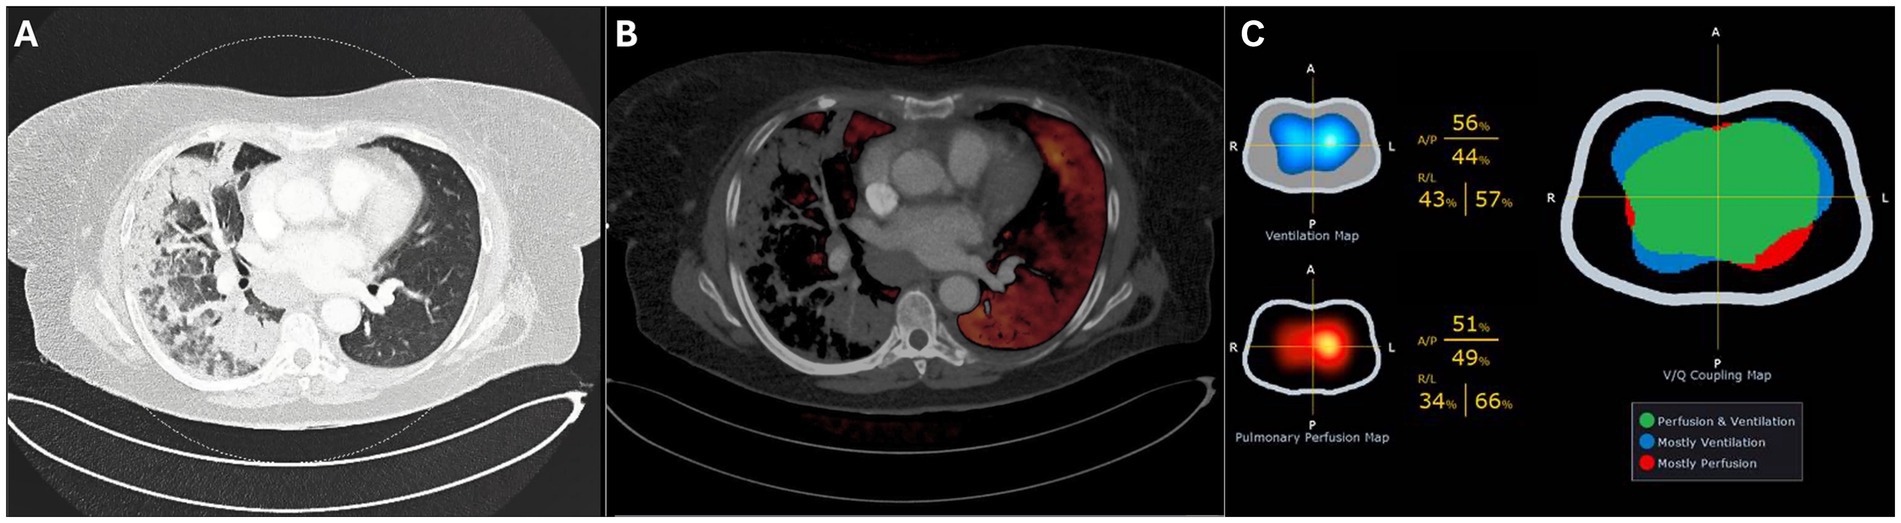

Upon admission to the ICU where high-flow nasal oxygen failed (flow 60 L/min, FiO2 1.0, ROX index 2.68), the patient was sedated and intubated. Following intubation, a dual-energy computed tomography (DECT) scan of the chest in supine position revealed extensive consolidation with ground-glass opacities, predominantly affecting the right lung, with no evidence of pulmonary embolism. The DECT findings suggested significant hypoxemic vasoconstriction (Figure 1), predominantly in the right lung. Subsequently, the patient was placed in a prone position to address severe respiratory failure. The first EIT-guided positive end-expiratory pressure (PEEP) trial was then performed in prone position.

Figure 1. Dual-Energy CT in supine position showing the pulmonary window (A) and perfusion overlay (B). Electrical impedance tomography (EIT) on day 4 (C) shows the ventilation and perfusion maps (left) and the ventilation–perfusion (V/Q) map (right), where matched regions appear in green, predominantly ventilated areas in blue, and predominantly perfused areas in red.

After 24 h (day two), the patient was turned to the supine position, and a repeated PEEP titration (from 24 to 12 cmH2O) guided by EIT was performed on the second day, again identifying an optimal PEEP level of 18 cmH₂O. During this titration, a substantial degree of alveolar collapse of 38.5% at the lowest PEEP step and increased overdistension of 40.8% at the highest PEEP step were observed. Notably, after decreasing the PEEP from 24 to 18 cmH2O there was no collapse but from 18 to 16 cmH2O, a sudden increase in alveolar collapse from 0 to 29.6% was detected, coinciding with a decline in respiratory system compliance from 52.2 to 31.4 mL/cmH₂O. Over the following 24 h (day three), the patient remained ventilated with a PEEP of 18 cmH₂O. PEEP titration on day four identified an optimal PEEP of 16 cmH₂O. Additionally, perfusion imaging was conducted through EIT favoring the left lung with a distribution of 34%/66% (right/left) and ventilation distribution of 43%/57% (Figure 1C).

We follow a standardized operating procedure (SOP) for PEEP titration, commencing at 10 cmH₂O above the previous setting, with a minimum of 24 cmH₂O, followed by a decremental trial in 6–8 steps until reduced compliance, oxygen desaturation to <90%, or collapse >10% was observed (to prevent derecruitment). In our patient, the protocol was limited to 20 cmH₂O on day one due to hemodynamic deterioration (ABP 72/58 mmHg, MAP 63 mmHg, desaturation to 79%). On day two, the PEEP trial was performed from 24 cmH₂O down to 12 cmH₂O (Figure 2). We acknowledge that the restricted range of PEEP values may have influenced the EIT-derived optimal PEEP, as algorithms assume that overdistension is 0% at the lowest PEEP and collapse is 0% at the highest step (8). Consequently, the relatively high lowest PEEP level may have underestimated overdistension and shifted the calculated crossing point toward a higher PEEP. This limitation underlines the importance of standardized EIT protocols, as recently emphasized by Scaramuzzo et al. (27). After the 18 cmH₂O PEEP step, collapse suddenly increased from 0 to 30% and reached 40% at 12 cmH₂O. According to our SOP, this high degree of collapse was the reason to terminate the trial at 12 cmH₂O. Based on the shape of the curve, this point most likely represents the airway closing pressure. EIT-guided PEEP titration was not performed on day 3 due to lack of experienced personnel, which may have reduced insight into disease progression. As shown in Supplementary Figure S1, the P/F ratio decreased between days two and three, with improvement after titration on day four. In retrospect, daily PEEP trials would have been preferable. Perfusion–ventilation mismatch measurements were performed only on day 4 (Figure 1C); although consistent with DECT results, conclusions remain limited given the single measurement.